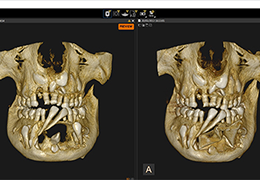

View X-Ray CT & MRI Scans Fast and Easily

FREE and easy to use 3D DICOM Viewer – for surgeons and patient education

Designed for surgeons, Pro Surgical 3D makes it easy to view patient scans quickly. Pro Surgical 3D facilitates the optimal 3D treatment and assessment workflows based on X-ray CT and MRI scans – and best of all, it’s FREE!

Everyone – including surgeons, patients and their loved ones – benefits from being better informed by the wealth of information buried within CT and MRI scans. Pro Surgical 3D gives surgeons more information to develop optimal treatment plans for patients. It also helps patients and their support group better understand their medical condition and proposed treatment options.

High-quality and fast 3D reconstruction and 3D rendering

Performs 3D reconstruction and volume rendering.

Side-by-side comparative assessment for pre- and post-operative scans.